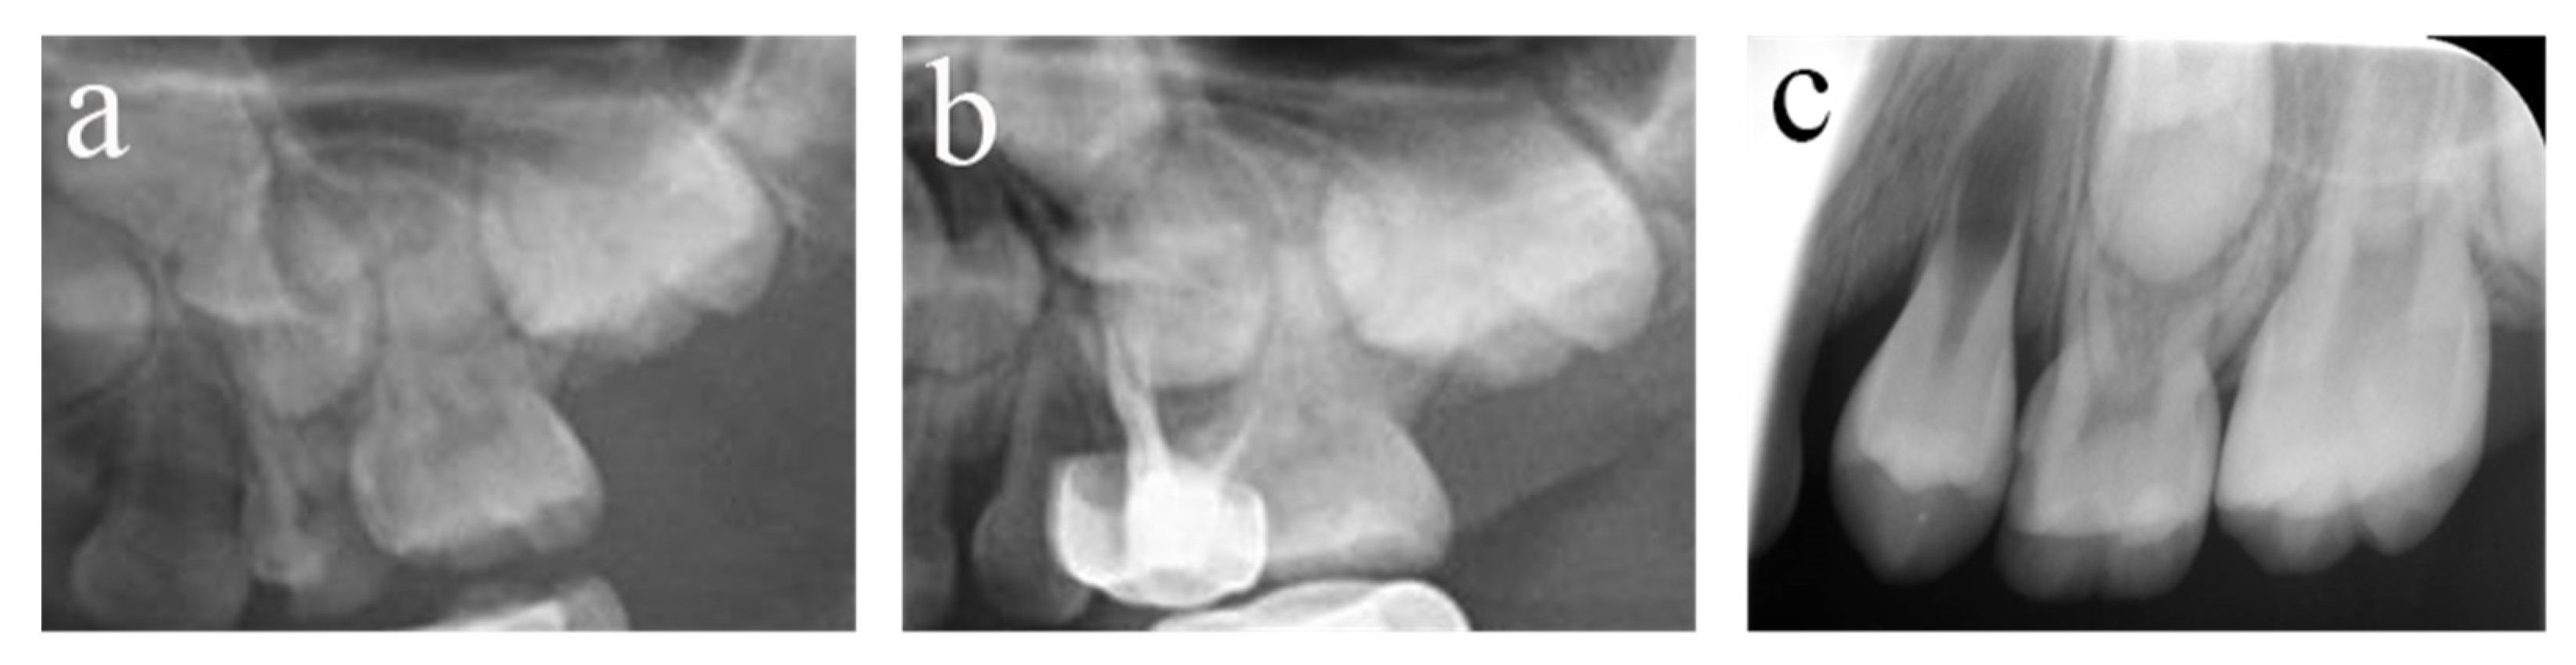

Figure 5.

#54 received pulpectomies under DGA with a 34-month follow-up period (65-month-old male child). (a) The preoperative radiograph revealed periapical radiolucency surrounding #54. (b) Radiograph taken one week postoperatively showing overfilling in the buccal root canals. (c) Twenty-six months after the operation, the root was completely absorbed, and the eruption direction of #14 was altered. Pulpectomies in #54 failed.